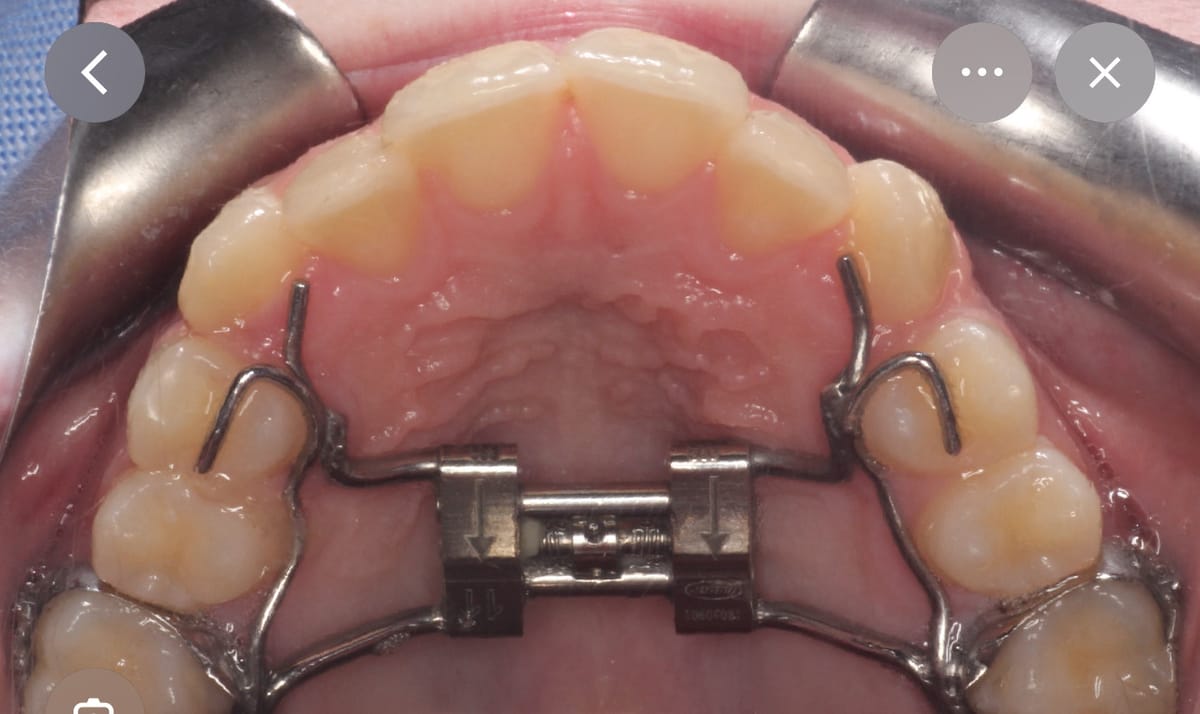

L'appareil d'expansion

L'expanseur palatin est fixé sur les molaires supérieures. Une vis centrale permet d'activer l'expansion. Chaque tour élargit le palais d'environ 0,25 mm.